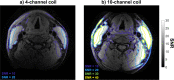

Methods: The proposed 10-channel receive coil was compared to a commercial 4-channel receive coil configuration using data acquired from phantoms and healthy volunteers (N = 9). The relative performance of the coils was assessed, by comparing signal-to-noise ratio (SNR), noise correlation, g-factor noise amplification, and the CNR between vessel wall and lumen using black-blood sequences. Patient data were acquired from 12 atherosclerotic carotid artery disease patients.

Results: The 10-channel coil consistently provided substantially increased SNR in phantoms (+77 ± 27%) and improved CNR in healthy carotid arteries (+62 ± 11%), or reduced g-factor noise amplification. Patient data showed excellent delineation of atherosclerotic plaque along the length of the carotid bifurcation using the 10-channel coil.

Conclusions: The proposed 10-channel coil design allows for improved visualization of the carotid arteries and the carotid bifurcation and increased parallel imaging acceleration factors relative to a commercial 4-channel coil design.